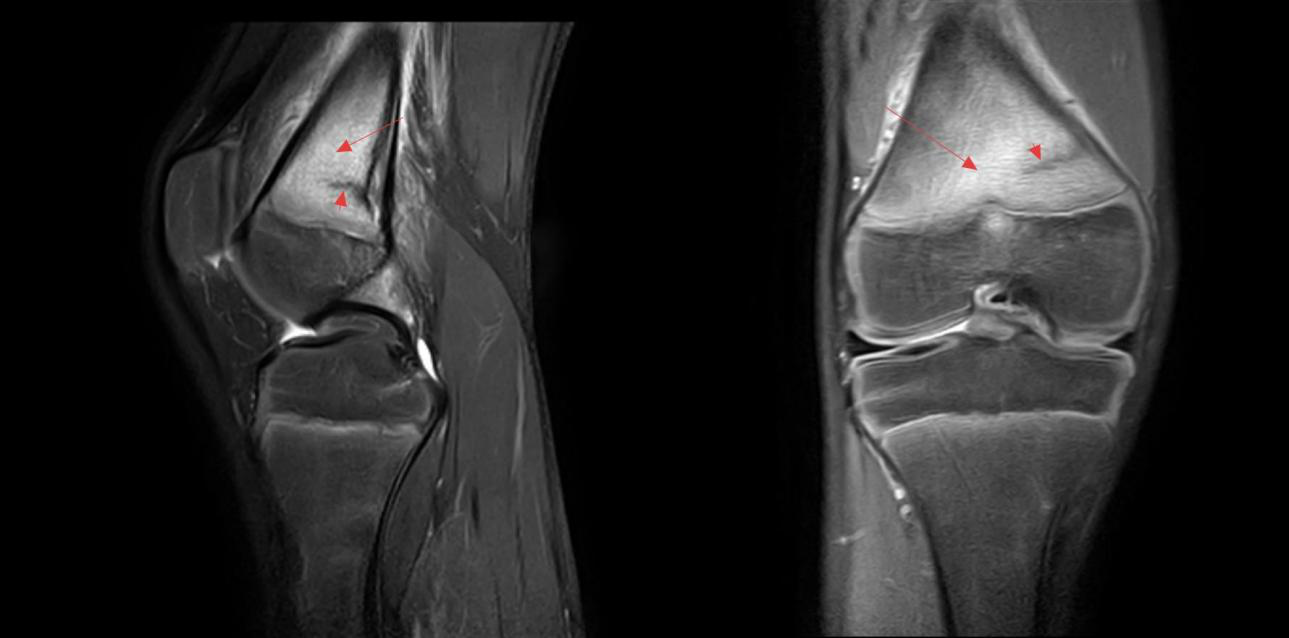

图中短箭头:骨折线 长箭头:骨髓水肿

这种骨折并非突发的外伤所致,而是由于骨骼长期反复承受过度负荷,超出了自身的修复能力,从而产生的细微骨裂。青少年正处于生长发育期,骨骼需在运动中变得强壮,但骤增的压力会让其“不堪重负”,尤其在跑步、跳跃等重复性高的运动中容易发生。

一旦出现运动后特定部位疼痛,且休息后不缓解甚至夜间加重的情况,就应高度警惕。许多应力性骨折在普通X光片上难以显现,极易被误认为肌肉拉伤。及时进行磁共振检查是明确诊断的关键,避免因延误治疗导致损伤加重。